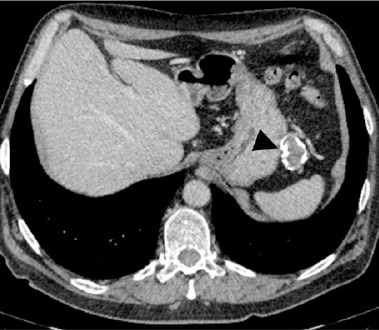

目的:本病例的目的是介绍对新发记忆障碍伴癫痫发作患者进行深入分析的意义。病例描述:我们报告一例61岁男性患者,因不明原因的记忆障碍和癫痫发作而入院。进一步检查显示存在抗lgi1(富含亮氨酸的胶质瘤失活1)抗体。腹腔计算机断层扫描显示胃和脾脏之间有肿块。组织病理学检查确定肿块为胃肠道肿瘤(GIST)。手术切除肿瘤后,症状明显减轻。肿瘤的早期诊断和治疗有助于患者的神经学和肿瘤学预后。评论:副肿瘤神经系统综合征是一种神经系统功能受损的临床症状,不是由局部肿瘤生长或转移引起的。目前公认的这种情况的潜在机制是发生在患者体内的自身免疫反应。作为对肿瘤存在的反应,一种被称为肿瘤神经抗体的抗体被产生,这种抗体随后被用于对抗神经系统细胞上的抗原。据我们所知,这是第一个也是迄今为止唯一一个抗lgi1抗体自身免疫性脑炎作为与GIST相关的神经副肿瘤综合征。

Case description: We present a case of a 61-year-old male patient who was admitted to the hospital due to unexplained memory disorders and seizures. Further examination showed the presence of anti-LGI1 (leucine-rich glioma-inactivated 1) antibodies. Computed tomography of the abdominal cavity revealed a mass located between the stomach and the spleen. Histopathological examination identified the mass as a gastrointestinal tumour (GIST). After the surgical removal of the tumour the symptoms were significantly reduced. The early diagnosis and treatment of the tumour contributed to favourable neurological and oncological outcomes for the patient.